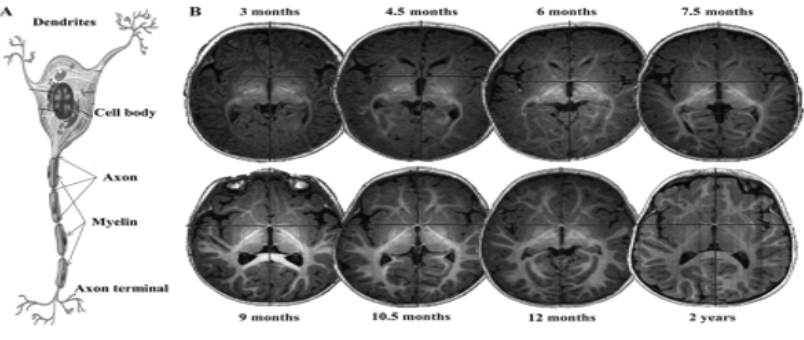

Нейровизуализация и диагностика

При показаниях проводится МРТ головного мозга, чтобы оценить последствия гипоксии и исключить структурные изменения.